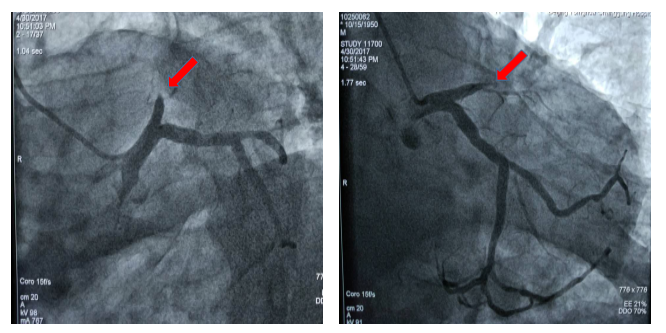

图1 患者术前冠脉造影显示冠脉血管前降支近段100%闭塞